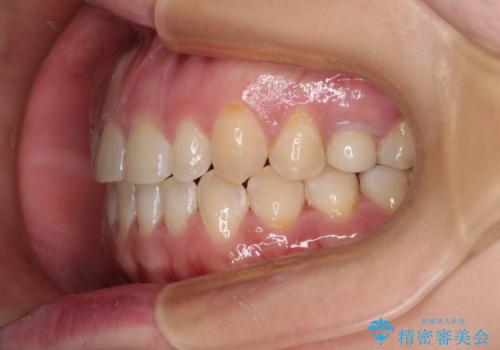

隙間の空いた歯列とボロボロの乳歯 インプラント治療と矯正治療

- 隙間の多い歯列や傾斜した奥歯、むし歯の酷い残存乳歯を気にして来院された患者様です。

歯列はワイヤー矯正にて改善することとしましたが、上下歯列にも隙間があったので、舌の突出癖を改善するトレーニングを徹底的に行うこととしました。

傾斜した下顎の奥歯は、矯正治療にてまずは歯軸を改善させ、隙間が閉じられるようであればそのままに、閉じられないようであればインプラント治療を行うこととしました。

上顎のむし歯の酷い残存乳歯は抜歯をし、矯正治療の途中でインプラントを埋入、矯正治療後に補綴治療を行うこととしました。